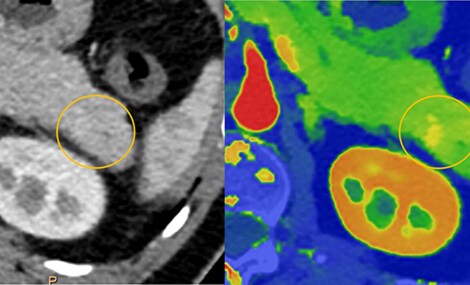

Verbesserte Gewebeanalyse mit Spectral-CT